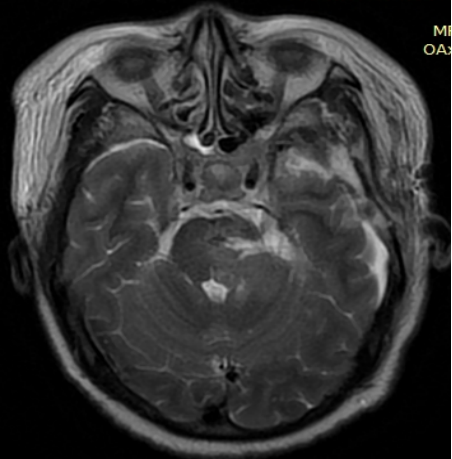

图三复查影像显示肿瘤全切

术中,在神经导航的实时引导下精准切除了脑干区肿瘤,同时清除了脑干血肿,解除肿瘤和血肿对脑干双重压迫,手术非常成功。术后病人即意识清醒,第二天肢体肌力由1级恢复到4级(正常肌力是5级)。经过7天的精心治疗,患者已能下地走路,并顺利康复出院。